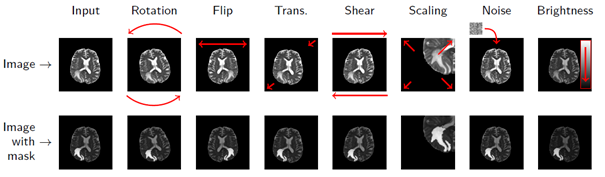

Unfortunately, the world is not fully labelled – we need to somehow generate ground-truth labels. Remember intra- and inter-rater variability? This is just one issue that makes the manual annotation process challenging. Besides, it is costly, time-consuming, and not super exciting… Fortunately, we can try to synthesize artificial examples based on existing training samples in the data augmentation process. Even very simple operations may lead to an increase in the training size considerably (Fig. 3).

Figure 3 [8]